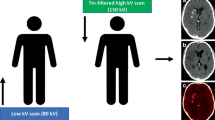

TwinSpiral DECT, a version of the dual spiral technology, is a recently introduced DECT technique for acquiring datasets at two different energy levels for spectral separation. First, a low kV scan is acquired, immediately followed by a high kV tin filtered second scan, resembling a single scan by minimizing the delay between the two scans. To the best of our knowledge, no previous study investigated this technique for neuroradiological applications.

A head CT imaging was performed using a single-source CT scanner (Somatom X.cite, Siemens Healthcare, Erlangen, Germany) in TwinSpiral dual-energy mode. Tube voltages were set to 80 and 150 kVp, the latter operated with tin (Sn) filtration, and with corresponding quality reference tube current-time products of 220 and 179 mAs, respectively, using automated tube current modulation (CAREDose4D) (Fig. 1). Further scanning parameters were as follows: slice acquisition, 2 × 0.6 × 64 mm by means of a z-flying focal spot; rotation time, 1.0 s; and pitch, 0.55. The mean volume CT dose index (CTDIvol) of the protocol was 43.7 ± 3.4 mGy.

Schematic mode of operation of a single-source TwinSpiral dual-energy CT: Two consecutive scans at a different energies (low and a high kV scan) are performed directly one after the other. From these two datasets, conventional mixed CT images (a), as well as dedicated reconstructions, such as color-coded iodine overlay images (b) and virtual non-contrast (VNC) images (c) can be postprocessed